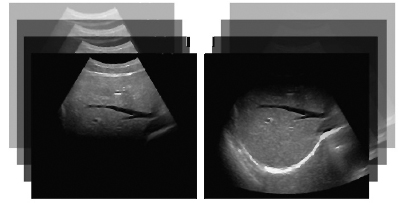

Технология «Компаунд» - формирование единого изображения на основе нескольких, зарегистрированных под разным углом, что повышает контраст изображения (слева до включения режима “компаунд”, справа - режим “компаунд” включен).